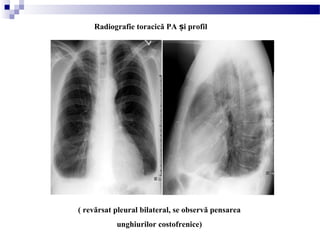

( revărsat pleural bilateral, se observă pensarea

unghiurilor costofrenice)

Radiografie toracică PA i profilș